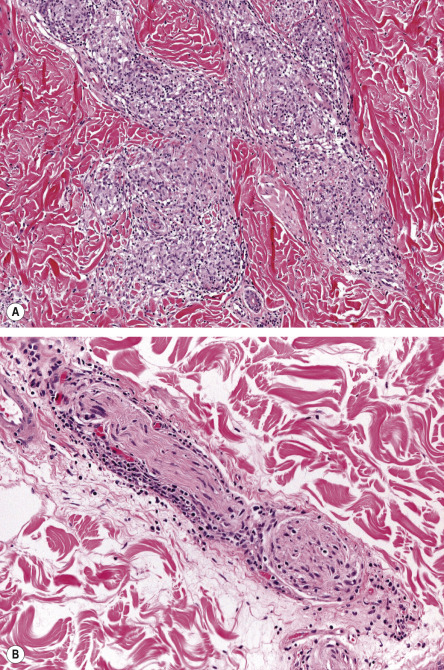

There are three basic histopathologic patterns observed in leprosy: lepromatous, tuberculoid, and borderline. In the lepromatous pattern, an infiltrate is seen in the dermis, subcutis, lymph nodes, abdominal organs (e.g. kidney, liver), testicles, and bone marrow. The infiltrate contains Virchow cells, which are macrophages with numerous bacilli as well as lipid droplets in their cytoplasm. In H&E-stained sections, these cells have a foamy appearance. The bacilli in leprosy can be detected by a Gram, Ziehl–Neelsen, or Fite (the most commonly used) stain, all of which stain the bacilli a bright red color. Methenamine silver stains are also useful for detecting fragmented acid-fast bacilli. Sudan III and Sudan IV (also known as scarlet red) were used historically and stain the bacilli black and red, respectively. For lesions in which bacilli are usually scant, it is recommended that at least six sections be examined before declaring them negative .

A band of normal-appearing dermis (Unna band or Grenz zone) separates the epidermis from the infiltrate, which is composed of plasma cells and lymphocytes in addition to Virchow cells ( Fig. 75.9 ). Both isolated bacilli and globi (clumps of bacilli) are seen in the dermis; when the patient is undergoing successful therapy, the organisms fragment and become granular. Cutaneous nerves demonstrate lamination of the perineurium, producing an onion-skin appearance. In the histoid variant, a well-circumscribed proliferation of spindle cells contains numerous bacilli, which typically line up along the long axis of the cell.

In the tuberculoid pattern of leprosy, a dermal granulomatous infiltrate is seen and may have a linear pattern following the course of a nerve ( Fig. 75.10 ). Epithelioid cells and Langhans giant cells are surrounded by lymphocytes. The cutaneous nerves are edematous, and there is an absence of organisms, even with special stains. Inflammation and fragmentation of nerve fibers in tuberculous leprosy differentiate it from sarcoidosis and other granulomatous disorders.